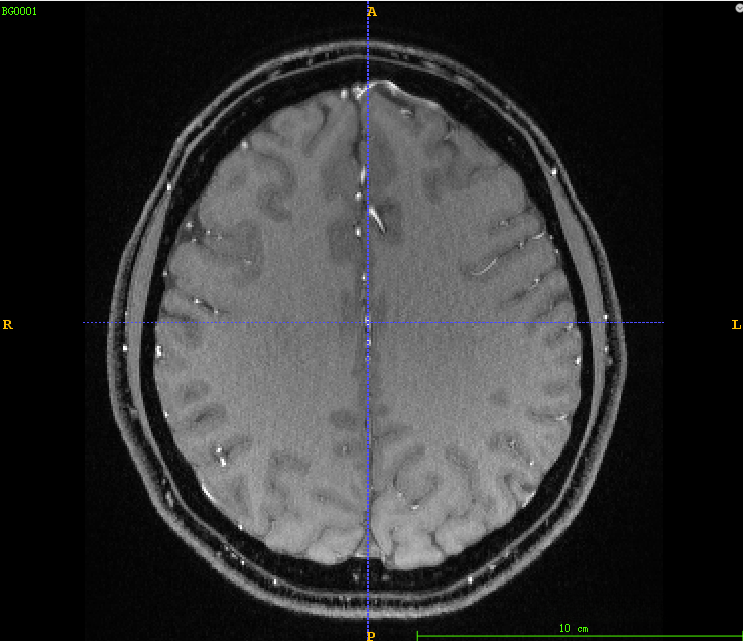

4、血管分割代码详解

4.1、采用itk的多尺度海森矩阵血管增强

4.2、 将增强后的血管归一化到0-255范围

4.3、 对归一化的血管进行固定阈值分割

代码:

def vessleSegment(pathDicom): sigma_minimum = 0.2 sigma_maximum = 3. number_of_sigma_steps = 8 lowerThreshold = 40 output_image = 'vessel.mha' input_image = itk.imread(pathDicom, itk.F) # 1 ImageType = type(input_image) Dimension = input_image.GetImageDimension() HessianPixelType = itk.SymmetricSecondRankTensor[itk.D, Dimension] HessianImageType = itk.Image[HessianPixelType, Dimension] objectness_filter = itk.HessianToObjectnessMeasureImageFilter[HessianImageType, ImageType].New() objectness_filter.SetBrightObject(True) objectness_filter.SetScaleObjectnessMeasure(True) objectness_filter.SetAlpha(0.5) objectness_filter.SetBeta(1.0) objectness_filter.SetGamma(5.0) multi_scale_filter = itk.MultiScaleHessianBasedMeasureImageFilter[ImageType, HessianImageType, ImageType].New() multi_scale_filter.SetInput(input_image) multi_scale_filter.SetHessianToMeasureFilter(objectness_filter) multi_scale_filter.SetSigmaStepMethodToLogarithmic() multi_scale_filter.SetSigmaMinimum(sigma_minimum) multi_scale_filter.SetSigmaMaximum(sigma_maximum) multi_scale_filter.SetNumberOfSigmaSteps(number_of_sigma_steps) itk.imwrite(multi_scale_filter.GetOutput(), "step1.mha") # 2 OutputPixelType = itk.UC OutputImageType = itk.Image[OutputPixelType, Dimension] rescale_filter = itk.RescaleIntensityImageFilter[ImageType, OutputImageType].New() rescale_filter.SetInput(multi_scale_filter) itk.imwrite(rescale_filter.GetOutput(), "step2.mha") # 3 thresholdFilter = itk.BinaryThresholdImageFilter[OutputImageType, OutputImageType].New() thresholdFilter.SetInput(rescale_filter.GetOutput()) thresholdFilter.SetLowerThreshold(lowerThreshold) thresholdFilter.SetUpperThreshold(255) thresholdFilter.SetOutsideValue(0) thresholdFilter.SetInsideValue(255) itk.imwrite(thresholdFilter.GetOutput(), "step3.mha")